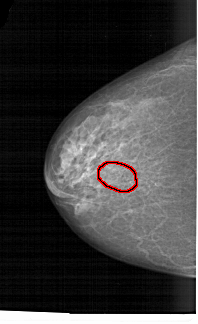

A_1455_1.LEFT_CC

LEFT_CC LINES 5821 PIXELS_PER_LINE 3556 BITS_PER_PIXEL 12 RESOLUTION 43.5 OVERLAY

FILE: A_1455_1.LEFT_CC.OVERLAY

TOTAL_ABNORMALITIES 1

ABNORMALITY 1

LESION_TYPE CALCIFICATION TYPE PLEOMORPHIC DISTRIBUTION CLUSTERED

ASSESSMENT 4

SUBTLETY 3

PATHOLOGY BENIGN

TOTAL_OUTLINES 1